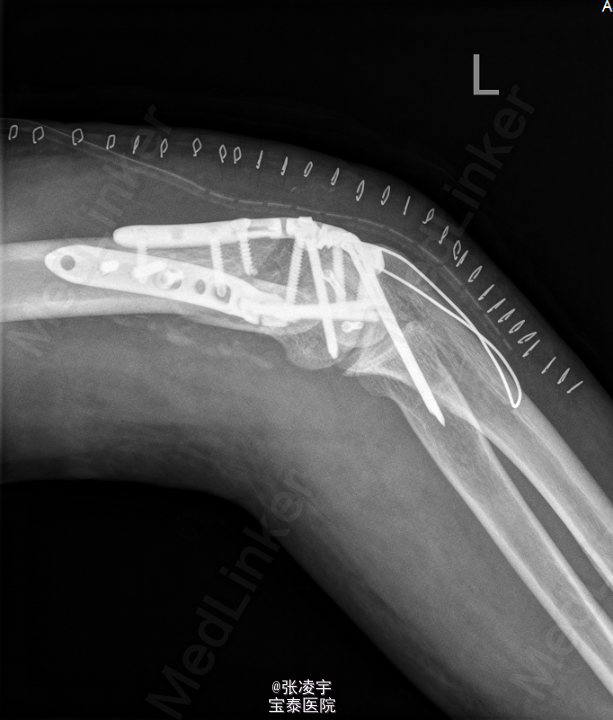

初步诊断: 1.左肱骨开放性骨折,右肘关节脱位? 行左肘关节韧带修补外固定架固定 。

术后注意功能锻炼防止粘连。